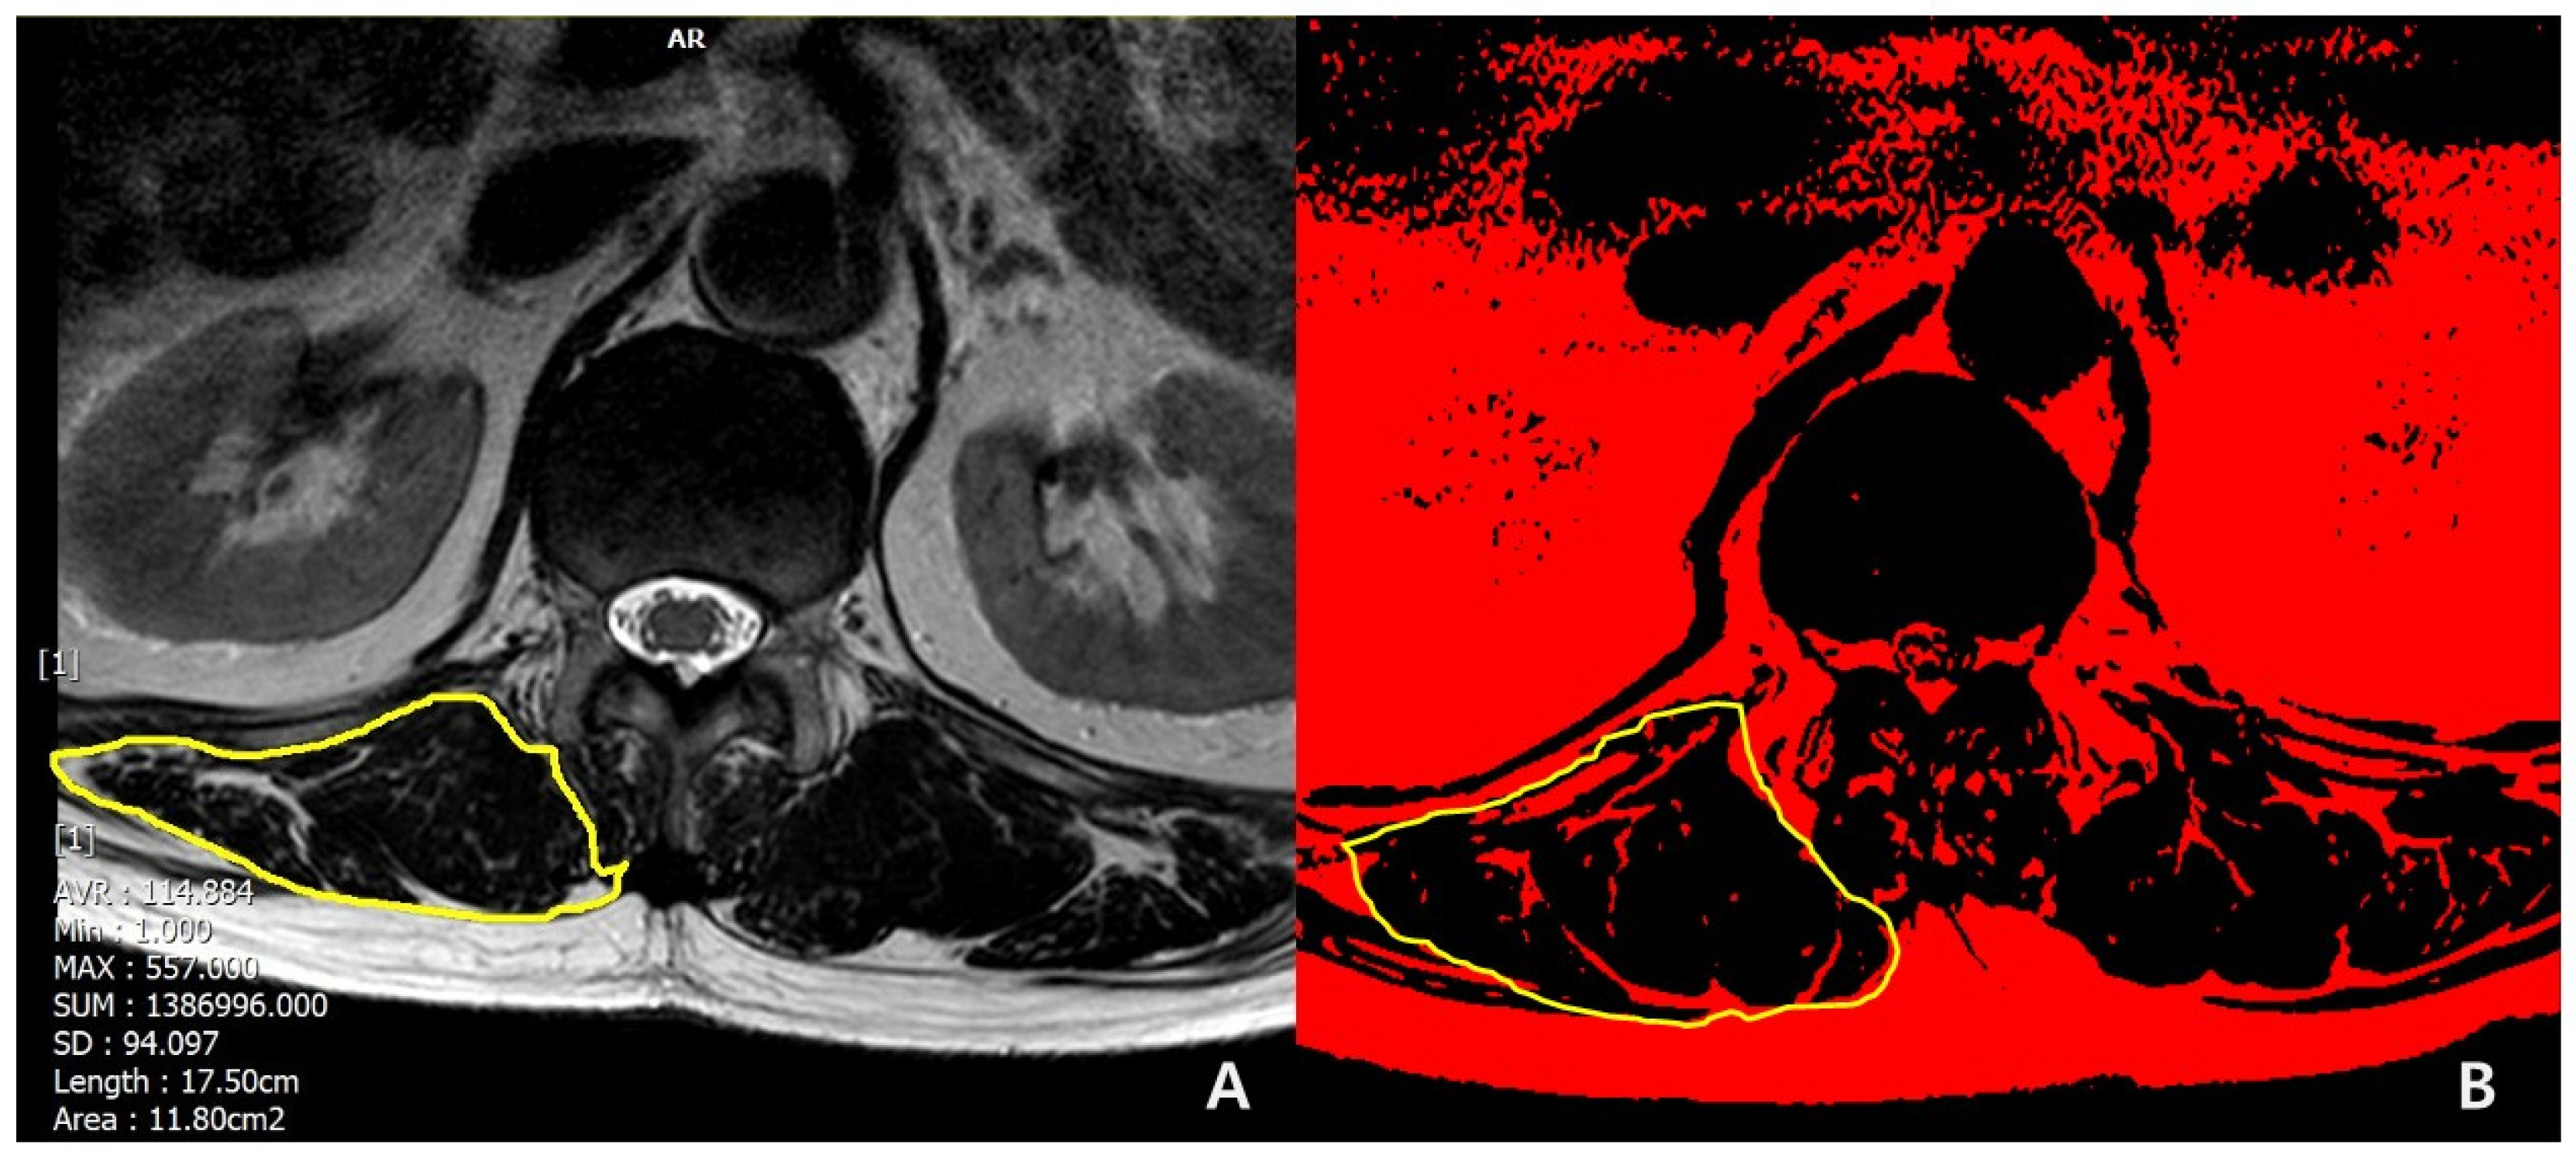

- Lee, J.C.; Cha, J.G.; Kim, Y.; Kim, Y.I.; Shin, B.J. Quantitative analysis of back muscle degeneration in the patients with the degenerative lumbar flat back using a digital image analysis: Comparison with the normal controls. Spine 2008, 33, 318–325. [Google Scholar] [CrossRef] [PubMed]

| Muscular quantity of T12-L1 (CSA of erector spinae), cm2 | 23.8 ± 4.2 | 32.2 ± 10.1 | <0.001 * |

| Muscular quality of T12-L1 (Fat infiltration in CSA of erector spinae) | <0.001 * | ||

| Mild to moderate (<50%), n | 4 | 21 | |

| Severe (≥50%), n | 13 | 3 | |